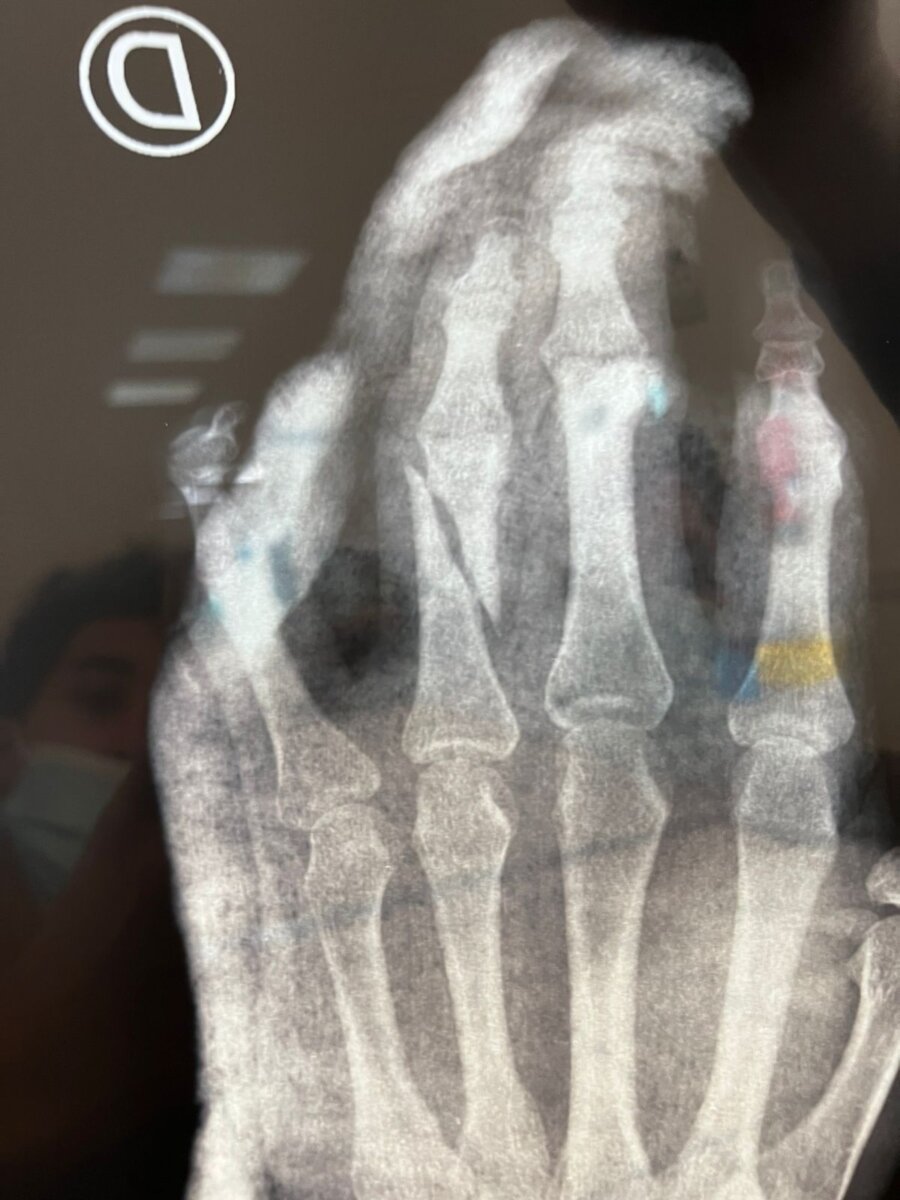

El matador hidrocálido Leo Valadez, después de su buena actuación en la Feria de Olivenza, sufrió un derrote en su primer toro, lo que provocó "fracturas diafisiaria oblicua de falange proximal del tercer y cuarto dedo de la mano derecha", por lo que mantendrá la mano enyesada durante las próximas tres semanas, para posteriormente comenzar la rehabilitación y poder reaparecer en la Feria de Arles en abril.